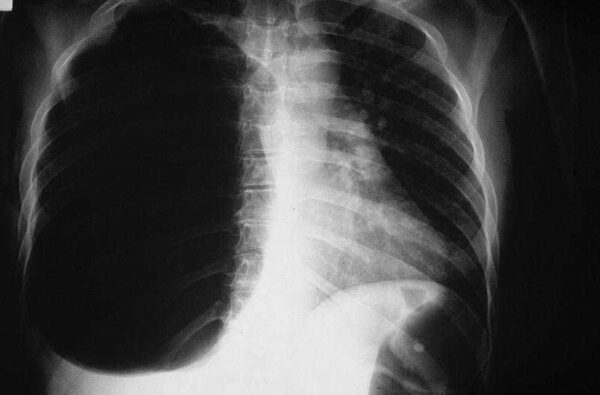

El neumotórax es una condición médica caracterizada por la presencia de aire en el espacio pleural, que es la cavidad entre las membranas que rodean los pulmones y la pared torácica. Dependiendo de su origen y relación con otras enfermedades o eventos, el neumotórax se clasifica en tres tipos principales: espontáneo (primario o secundario), traumático e iatrogénico.

- Neumotórax espontáneo primario: En este tipo, el neumotórax se desarrolla sin una causa aparente y sin la presencia de una neumopatía subyacente. Ocurre con mayor frecuencia en individuos jóvenes y delgados, especialmente en hombres fumadores. La teoría detrás de su desarrollo implica la presencia de pequeñas bolsas de aire (llamadas blebs o bullas) en la superficie del pulmón, que se rompen y liberan aire al espacio pleural, causando el colapso parcial del pulmón afectado.

- Neumotórax espontáneo secundario: En este caso, el neumotórax es una complicación de una enfermedad pulmonar subyacente, como enfermedad pulmonar obstructiva crónica (EPOC), asma, fibrosis pulmonar, infecciones pulmonares, quistes pulmonares, entre otras. La enfermedad subyacente debilita los tejidos pulmonares, lo que aumenta el riesgo de formación de bolsas de aire o la ruptura de bullas, llevando al neumotórax.

El neumotórax traumático es resultado de un traumatismo directo en el tórax, como una lesión penetrante (por ejemplo, una herida de arma blanca o de fuego) o una lesión contusa (por ejemplo, una fractura de costilla). El trauma causa una comunicación entre el aire atmosférico y el espacio pleural, lo que provoca la acumulación de aire y el colapso pulmonar. Los neumotórax traumáticos pueden ser leves o graves, dependiendo de la magnitud del daño.

En casos graves de neumotórax, especialmente en los neumotórax traumáticos, puede ocurrir un neumotórax a tensión. Esto sucede cuando el aire entra al espacio pleural durante la inspiración, pero no puede salir durante la espiración debido a un mecanismo de válvula unidireccional. Como resultado, el aire atrapado ejerce presión sobre el pulmón y los órganos mediastínicos, lo que causa una compresión peligrosa y potencialmente mortal.